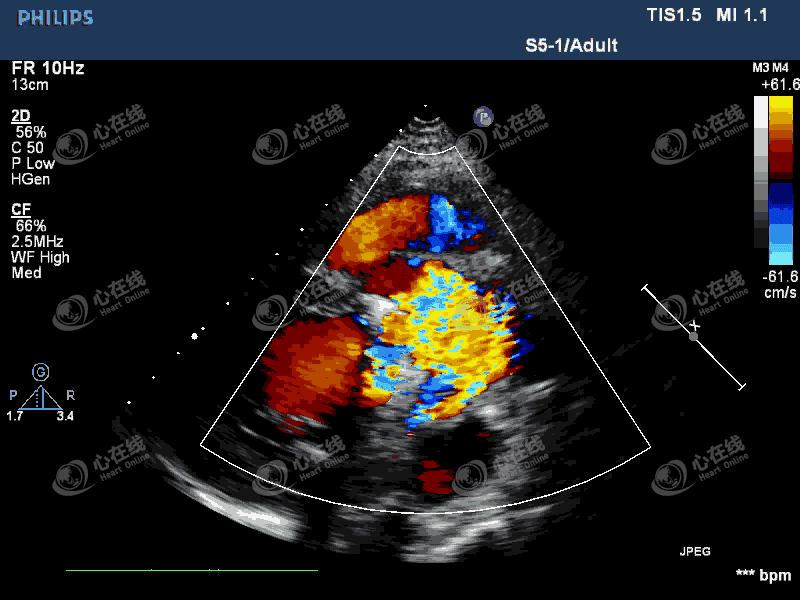

图2 左室长轴切面:彩色多普勒示,机械瓣瓣环外侧可见中量血流信号进入左室,另可见机械瓣中心性反流信号。主动脉根部膜样回声破口处可见血流信号,来自主动脉,并穿梭于该无回声区内。